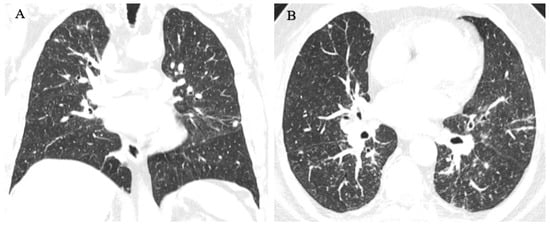

3.1.1. Case 1

3.1.2. Case 2